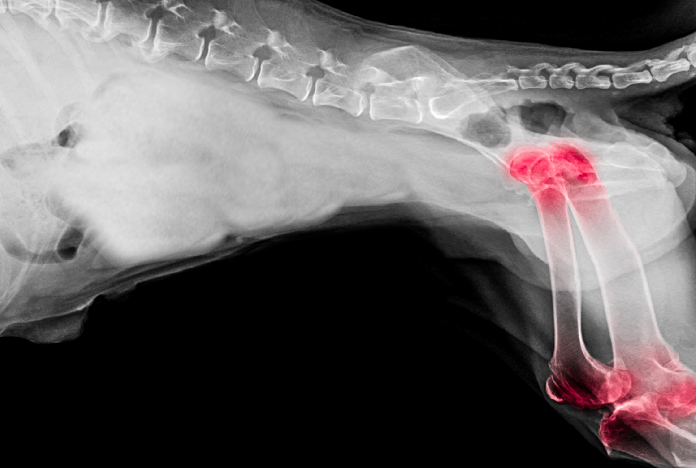

Veterinärmedizin

Immer mehr Menschen wollen ihren Haustieren ein gutes und langes Leben ermöglichen. Mit ihrer hohen Biokompatibilität und gleichzeitig hoher Festigkeit und Verschleissbeständigkeit eignen sich unsere Oxidkeramiken hervorragend für dieses Ziel. Mit unserer Erfahrung und unserem Knowhow aus der Orthopädie für Humanmedizin bieten wir beste Voraussetzungen für den veterinärmedizinischen Bereich.